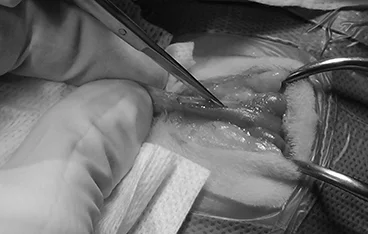

외이도 종괴, 외이염&중이염&내이염

TECA+LBO / VBO

• TECA+LBO 수술 전

TECA+LBO 수술 후